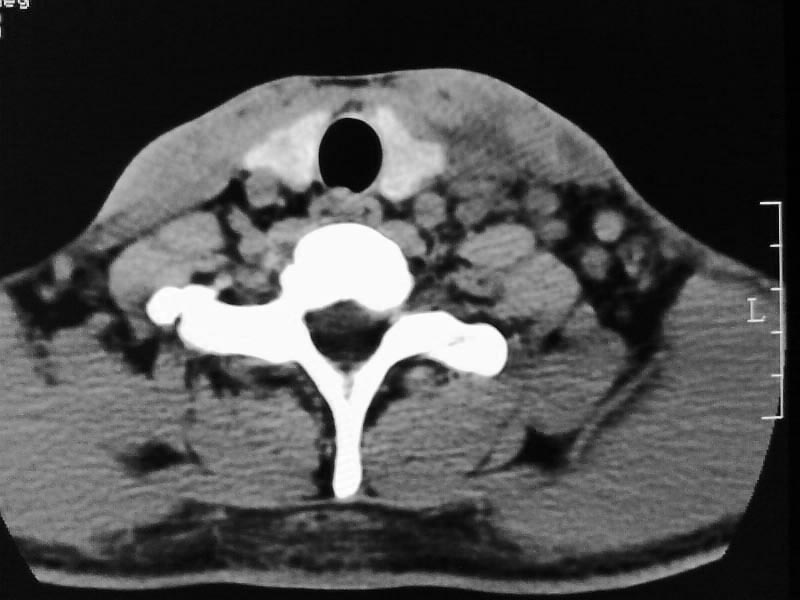

以下是引用余辉在2009-5-3 11:36:00的发言:[br]左侧胸锁乳突肌下方不规则肿物影,边界不清,内部密度不均,左侧颈外侧区脂肪增多,多发淋巴结肿大,考虑淋巴或神经来源肿瘤可能性大,不除外淋巴结炎,肌源性肿瘤及增生性肌炎等,活检